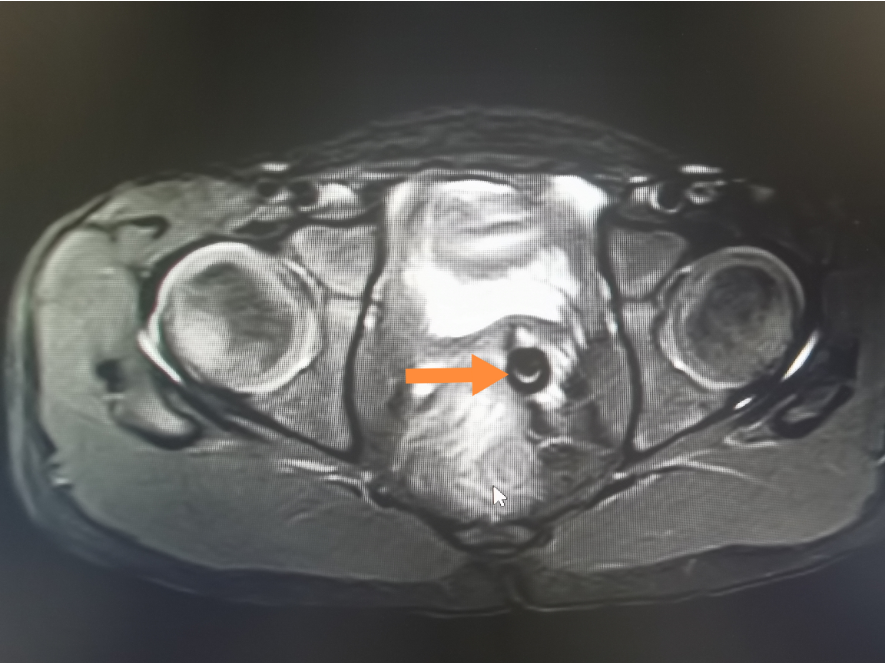

在给患儿完善了核酸检测及磁共振MRI检查后,医生发现报告结果提示阴道上段有两枚类圆形异物影。

在进一步肛查后,检查结果也显示可扪及阴道上段有两枚圆形的异物。

引发腹痛的原因有很多,比如囊肿等,鉴于孩子腹痛已经挺长时间了,医生建议家长先带孩子做影像学检查,检查结果提示有尖锐的物品在阴道穹隆-宫颈区里,正是这个“尖东西”引起的腹痛,医生当即意识到有异物,给孩子做了手术。